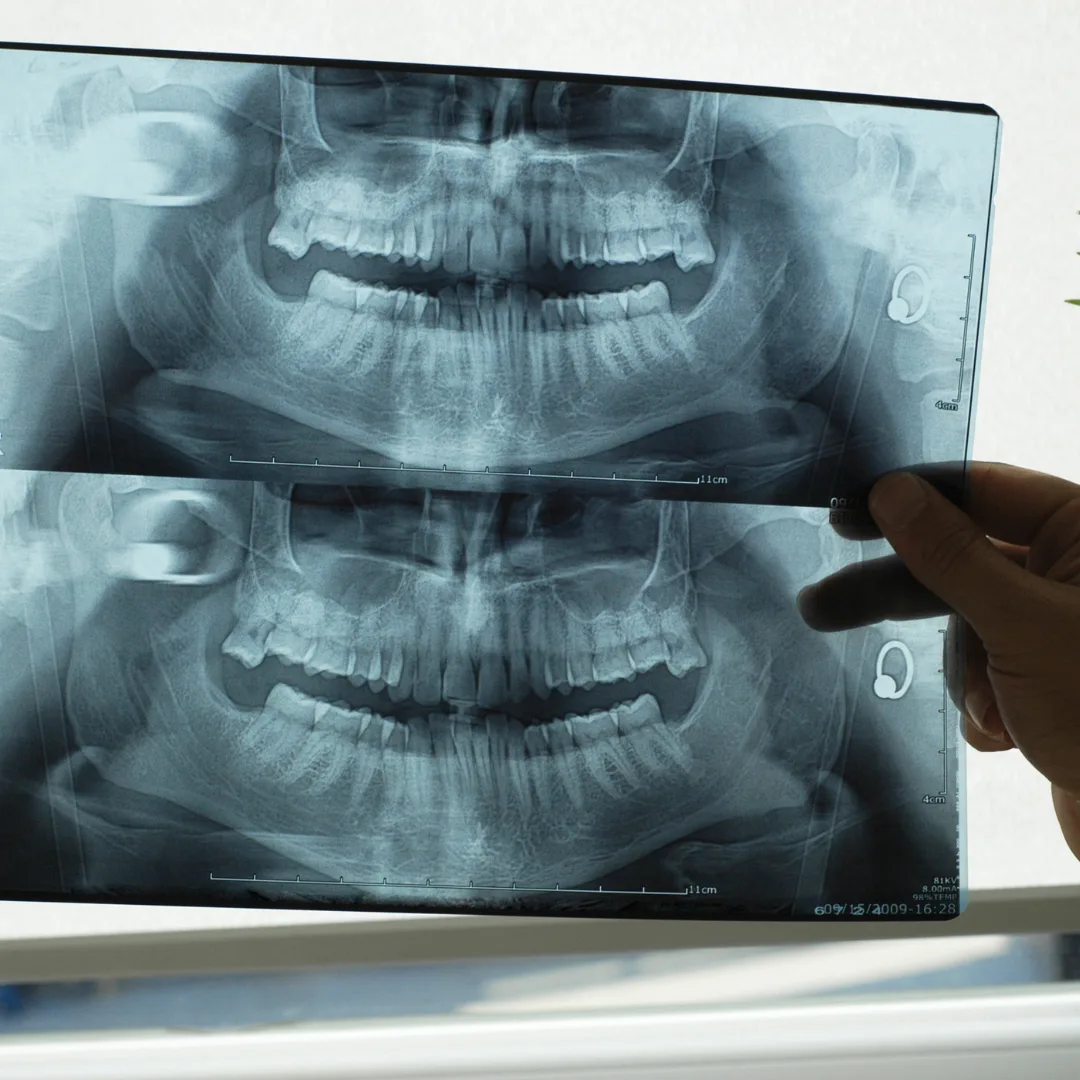

Panoramic X-rays: A single image showing all teeth, the entire jaw, and the TMJ. Panoramic X-rays reveal wisdom tooth position, jaw fractures, cysts, and large lesions. New patients and those with wisdom tooth concerns get panoramic X-rays.

Bitewings show the crowns of teeth and detect cavities. Periapical X-rays show an entire tooth from crown to root tip, revealing root infections and bone loss. Panoramic X-rays show all teeth and jaw structure. 3D cone beam CT imaging provides detailed information for implant planning and complex cases.